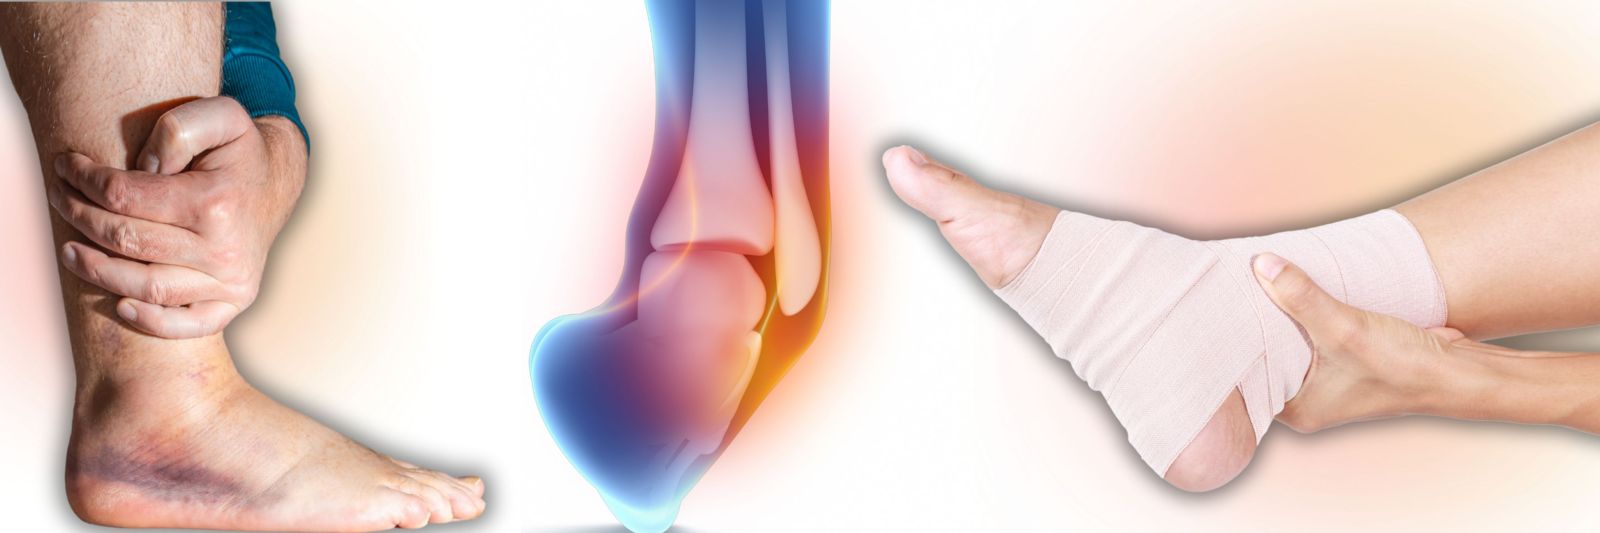

هنگامی که یک رباط بیش از حد کشیده یا پاره می شود، منجر به چیزی می شود که از نظر فنی به آن رگ به رگ شدن می گویند. بسیاری از رگ به رگ شدن ها به طور ناگهانی یا در اثر زمین خوردن، حرکت نامناسب یا ضربه اتفاق می افتد.

پیچ خوردگی معمولا در مچ پا، زانو یا مچ دست اتفاق می افتد. به عنوان مثال، یک گام اشتباه می تواند باعث شود که مچ پای خود را در موقعیتی نامناسب بپیچانید، رباطی را بشکافید و باعث بی ثباتی یا لرزش مچ پا شود. ممکن است هنگام آسیب دیدگی صدای پارگی بشنوید یا احساس پارگی کنید. زمانی که دست دراز کرده خود را برای شکستن زمین دراز میکنید، مچ دست اغلب رگ به رگ میشود، فقط برای اینکه مچ دست به عقب باز شود. این افزایش کشش رباط را بیش از حد کشیده می کند.

علائم رگ به رگ شدن رباط عموماً شامل درد، تورم و کبودی در ناحیه آسیب دیده است. ممکن است مفصل شل یا ضعیف شود و نتواند وزن را تحمل کند. شدت علائم شما بسته به اینکه رباط بیش از حد کشیده شده باشد یا واقعاً پاره شده باشد، متفاوت خواهد بود.

تشخیص تفاوت بین آسیب رباط ها و تاندون ها به تنهایی ممکن است سخت باشد. هر زمان که درد و تورم داشتید، برای تشخیص ماهرانه و برنامه درمانی موثر به پزشک مراجعه کنید.

در این بین، چه فشار یا رگ به رگ شدن، درمان فوری به طور کلی یکسان است. پزشکان توصیه می کنند:

- باقی مانده: سعی کنید قسمت آسیب دیده بدن خود را بی حرکت نگه دارید تا زمانی که بهبودی به خوبی انجام شود. این ممکن است با استفاده از بریسهای بیحرکتی و عصا در صورت نیاز آسانتر باشد.

- یخ: یخ را در حوله ای بپیچید تا از پوست محافظت کنید و سپس ناحیه آسیب دیده را به مدت 20 دقیقه هر بار، چند بار در روز، در حالی که بهبود می دهید، یخ کنید.

- فشرده سازی: با استفاده از بانداژ فشاری ورم را کاهش دهید. پانسمان را طوری بپیچید که محکم باشد اما به طور ناراحت کننده ای سفت نباشد.

- ارتفاع: بالا نگه داشتن قسمت آسیب دیده بدن از قلب می تواند به کاهش تورم و بهبودی کمک کند.

- دارو: داروهای ضد التهاب و مسکن های بدون نسخه، که در صورت نیاز مصرف شوند، ممکن است به کاهش درد و تورم شما کمک کنند.